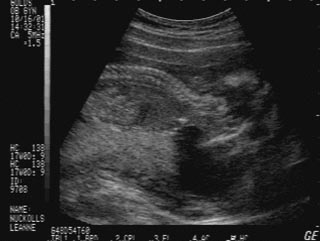

![]() Alex's very first photo: 17 weeks gestation (Oct. 16) The following week, Leanne felt him kick for the first time. |